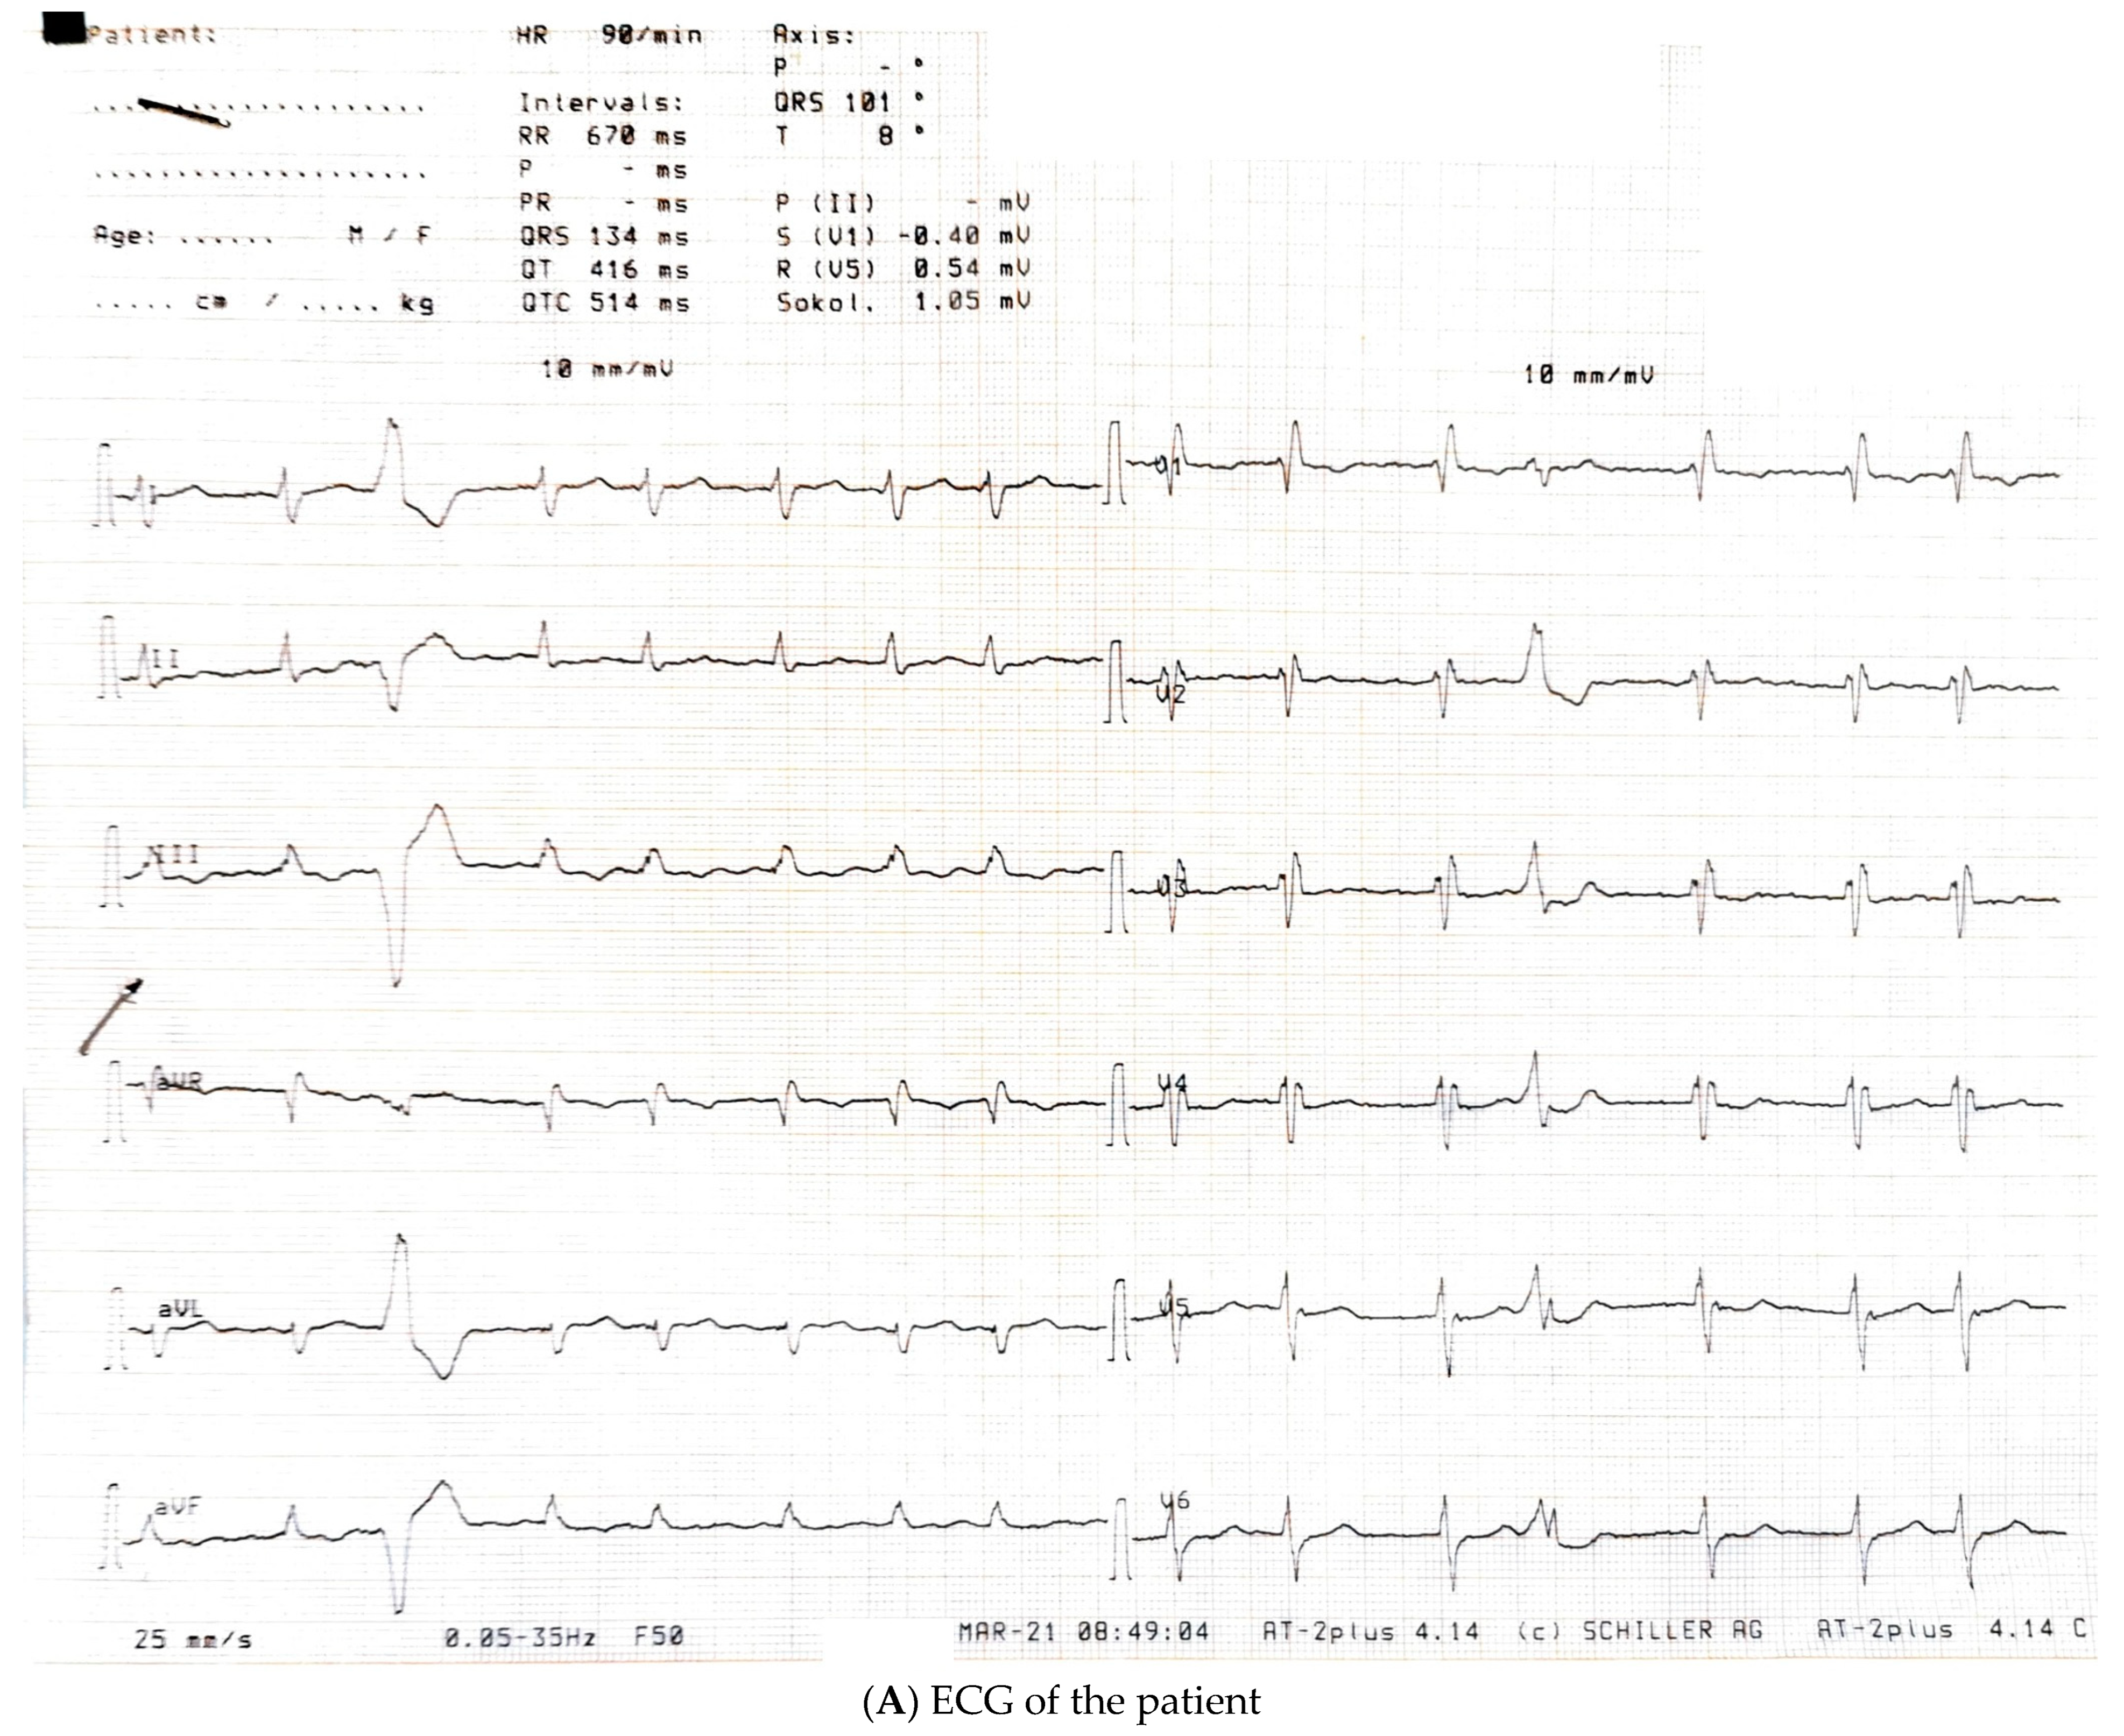

2. Detailed Case Description

| March 2021, age 45 | First episode of decompensated heart failure, NYHA III-IV class; A new episode of persistent AF, duration longer than two months | Management of failure according to guidelines; TEE not performed due to INR not being in target; Asymmetric left ventricular hypertrophy and reduced ejection fraction noted; Further diagnostic work-up recommended—cardiac magnetic resonance (CMR) and genetic testing; Test for Anderson–Fabry disease—negative; CMR study positive for cardiomyopathy with diffuse fibrosis, possibly hypertrophic or infiltrative. | At admission: Amiodarone 400 mg; Torasemide 20 mg; Irbesartan 75 mg; Acenocoumarol; At discharge: Torasemide 50 mg; Spironolactone 50 mg; Acenocoumarol; Bisoprolol 5 mg; Sacubitril/valsartan 2 × 24/26 mg; Allopurinol 150 mg; Dapagliflozin 10 mg |